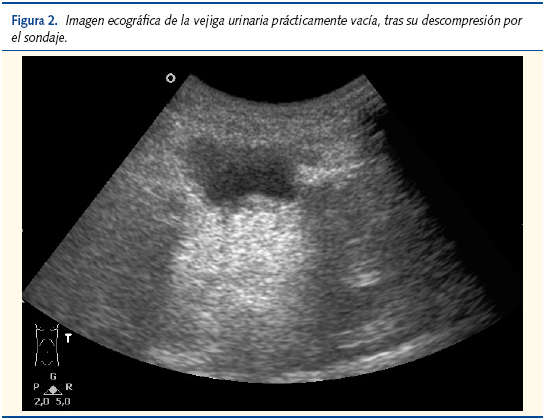

A continuación, se procedió a resolver la sobredistensión vesical mediante sondaje urinario con pinzado periódico, que permitió la evacuación de 450 ml de orina. El dolor de la niña se fue resolviendo de forma progresiva. En la ecografía de control se constató la desaparición del globo, así como la ausencia de imágenes de invaginación intestinal.